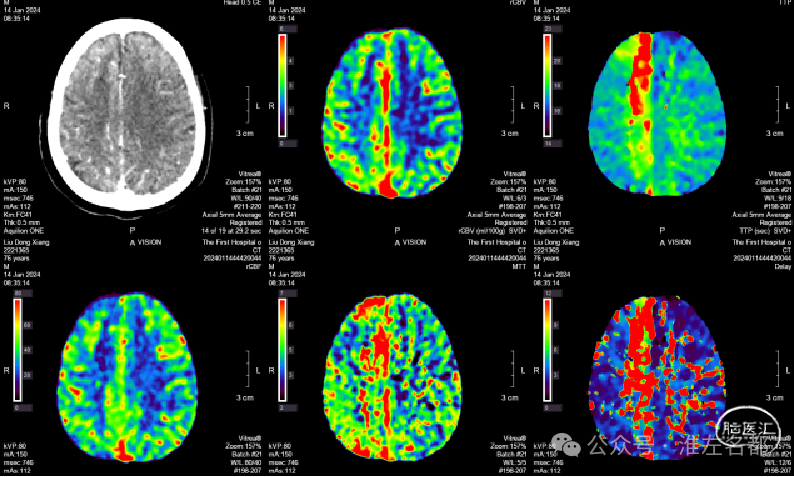

急诊多模式CT

CT平扫:未及明确异常。

颅脑CTA:右侧大脑前动脉A2段局部管腔严重狭窄,右侧大脑前动脉A1段未发育,左侧大脑前动脉A1段粗大。

颈部CTA:所见脑供血动脉未见明确异常。

脑CTP:右侧大脑前动脉供血区局部TTP延长,相应区域CBF和CBV未见明显异常。

2024-01-14 08:36

复查多模式CT

CT平扫:双侧胼体膝部和右侧额顶叶皮质多发梗死低密度影。

CTA:右侧大脑前动脉原A2段狭窄位置管腔闭塞。

脑CTP:右侧大脑前动脉供血区较大范围TTP显著延长。